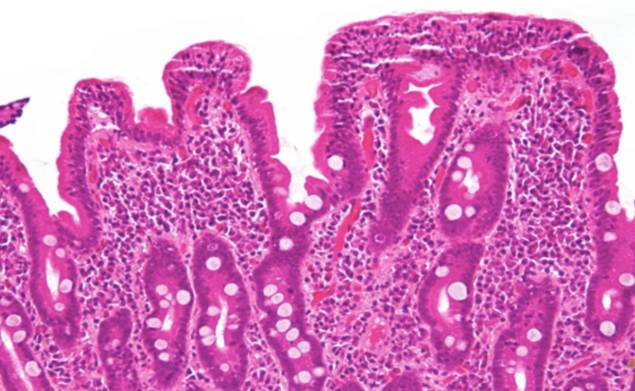

镜下所见:肠绒毛变钝、萎缩

乳糜泻患者的组织学异常改变,包括小肠绒毛部分至全部萎缩,隐窝延长,绒毛/隐窝比下降,肠上皮内淋巴细胞增多,固有层浆细胞、淋巴细胞、肥大细胞和嗜酸性细胞浸润:此外可见小肠刷状缘缺乏、肠上皮细胞异常变平。